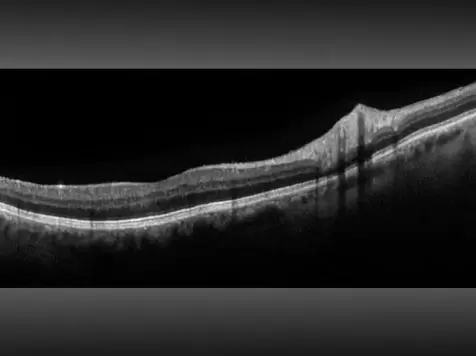

Retina Imaging/ Optos Monaco with OCT

Optomap retina imaging

OCT= Optical Coherence Tomography: uses light waves to take cross-section images of the retina, macula, optic nerve.

Optos Monaco combines optomap ultra-widefield technology with SD-OCT creating a fast, convenient, multi-modal imaging tool. Monaco can produce a 200°, single-capture retinal images of unrivaled clarity and can display a six-image overview including color, AF, and OCT of both eyes in as little as 90 seconds.